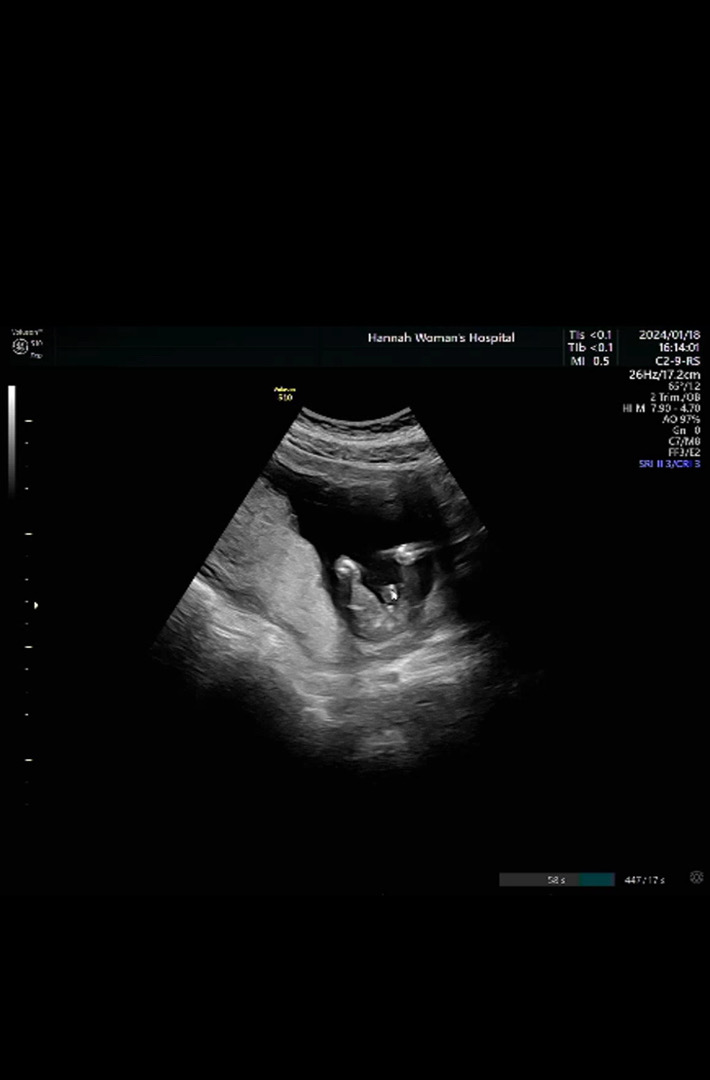

19주 정밀초음파 했는데 딸로 결정났습니당^^!!

아들일까요 딸일까요…ㅠㅠ

15주쯤 의사선생님께서 보이는게 없네요~ 하면서 딸같다는 느낌으로 말씀하셨는데 오늘 16주 1일에 검진 갔더니 애매하다고 하시더라구요.. 딸이라고 생각하고 있었는데,,, 어떻게 보이시나요?ㅠㅠ

아들에 한표요! 딸은 가랑이가 미끈해요

탯줄 밑에 뭐가 보이는데 아들 같아보입니다!

저기 마우스 있는 부분은 탯줄인거같고 밑에 점이 보이는데 아들이지않을까요..?ㅎㅎㅎ